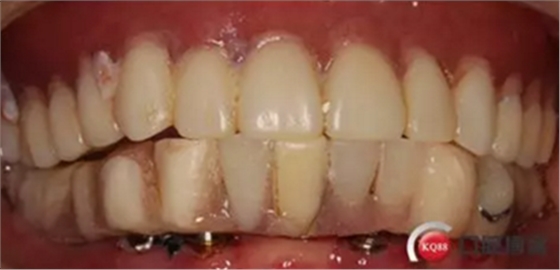

下頜無牙頜種植修復過程

病例簡介:患者:李女士,71歲

下頜假牙戴不穩(wěn),要求固定修復;

現(xiàn)病史:下頜假牙戴了多年,最近有顆牙脫落戴不穩(wěn)求診

檢查:上頜無牙頜假牙穩(wěn)定性尚可,下頜3435364243殘根;33殘冠1-2度松動,其他牙齒缺失;CBCT檢查:下頜牙槽骨前牙區(qū)骨高度足,后牙區(qū)骨高度最低為8mm,骨寬度足。

2.診斷:牙列缺失

3,治療計劃:依據(jù)檢查及主訴,擬323436434446植入6顆osstem植體,無即刻拔除33殘冠目的方便戴過渡性臨時活動義齒,6個月后完成二氧化鋯冠橋修復